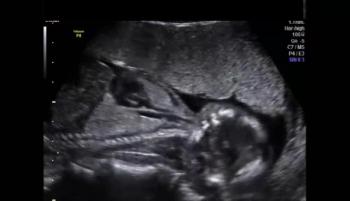

QUIZ: These images are of the fetal heart reveal an abnormality. Can you identify it?